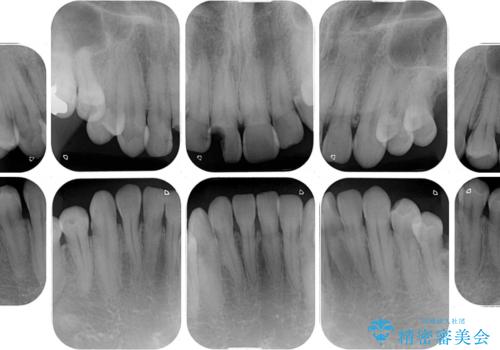

- 前歯や奥歯の虫歯を放置しており、それらの治療を契機に真っ白な歯にしたいとのことで来院された患者様です。

咬み合わせを改善するに当たって、抜歯しなければならない歯や歯列の改善が必要な箇所があったため、矯正治療やインプラント治療から始めていくこととしました。